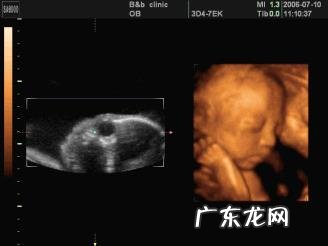

四维最佳期检查的时候 , 孕妈妈能够通过四维检查屏幕很清楚的看到胎儿在肚子里各种活动 , 打哈欠、吐舌头、吞咽羊水、拳打脚踢、翻跟头、睡觉、甚至沉思状;还有些皮皮的宝宝捂着脸不让看 , 或者转过身去等等;不仅可以拍下宝宝可爱的照片 , 还能够进行排畸检查 。

一般孕24周是检查四维彩超的最佳时间 , 四维彩超不仅囊括了传统b超所有的检测范围 , 还能对胎儿的体表进行检查 , 能够全方位、多角度地观察宫内胎儿的生长发育情况 , 如果有异常发生 , 也能尽快地采取应对措施!